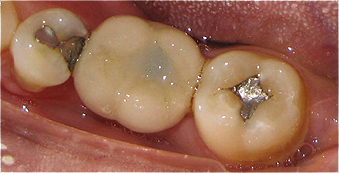

Resultado de colocação de implante dentário na Clínica São Filinto

Caso 8 - Colocação de implantes dentários para reabilitação com prótese fixa em zircónio cerâmica no 4º quadrante.

![]() |